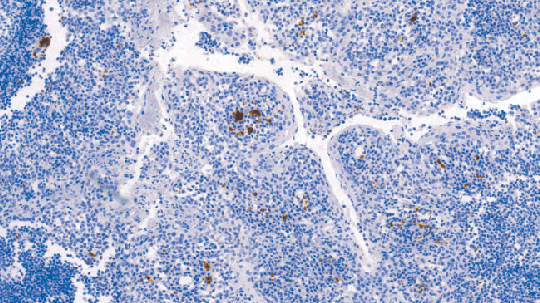

CD61抗原也称为GPllla,是分子量为105kD的糖蛋白,存在于血小板、单核细胞、内皮细胞、平滑肌细胞、B细胞、巨噬细胞、肥大细胞和成纤维细胞中。CD61抗原在血小板聚集中发挥作用,并且还是纤维蛋白原、纤维连接蛋白、vonWillebrand因子和玻连蛋白的受体。据报道,在格兰茨曼(Glanzmann) 血小板无力症的患者中极少或者不表达CD61抗原。大多数巨核细胞白血病的病例表达CD61抗原。

- 阳性部位:胞膜,胞质

- 适用组织:石蜡切片

- 预处理:热修复

文献和实验CD61 分子 CD61 常用单克隆抗体或代号: Y2/51,CLB- thromb/1;(VNR- b 链,integrin b 3) 主要表达细胞: Pt,Meg [Pt] 分子质量(kDa)和结构: gp105,血小板GPⅢa,与CD51组成VNR,与CD41组成a Ⅱbb 3 功 能: 血小板凝集和活化 CD61 Aka platelet glycoprotein IIb